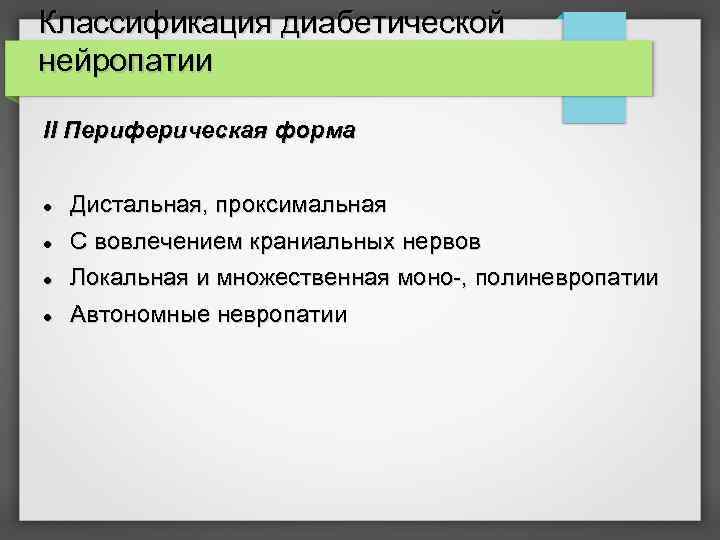

Классификация диабетической нейропатии II Периферическая форма Дистальная, проксимальная С вовлечением краниальных нервов Локальная и множественная моно-, полиневропатии Автономные невропатии